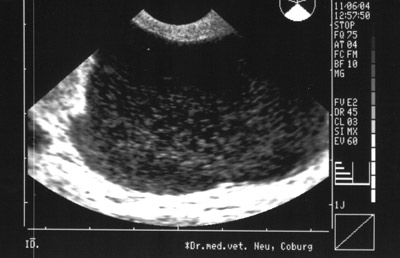

Neben der Trächtigkeit sind pathologische Veränderungen an der Gebärmutter abzugrenzen. Hier in diesem Beispiel handelt es sich um eine Gebärmuttervereiterung, eine „Pyometra“ die man als eitergefüllte Hohlräume auf dem Bild schön erkennen kann. Nach Stellung der Diagnose konnte der kleine Foxterrier schnell operiert werden und erfreut sich wieder bester Gesundheit.